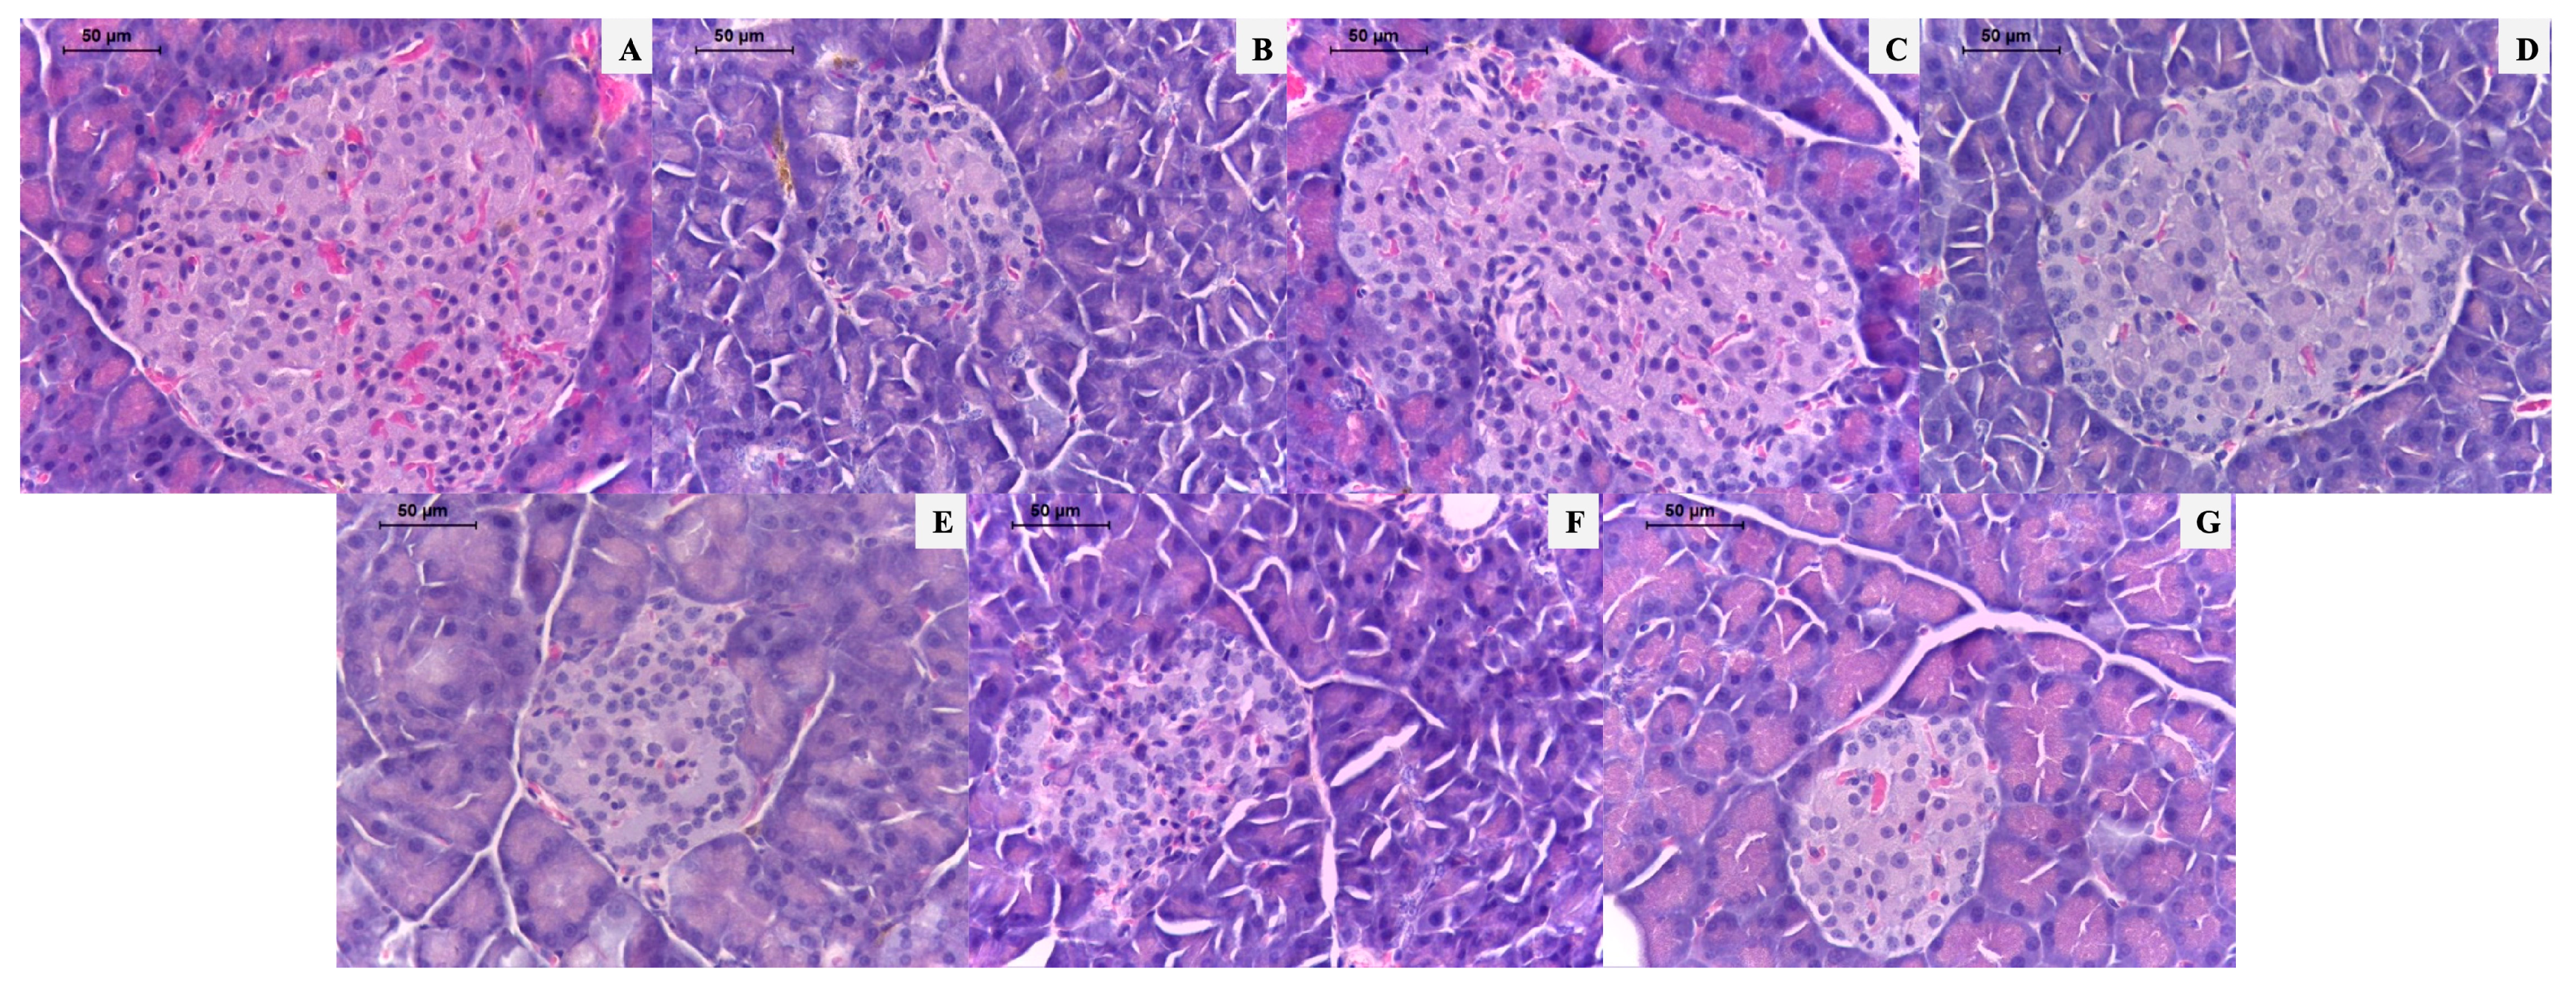

| Langerhans islet size (μm) | 249.0 ± 29.3 * | 132.9 ± 22.4 † | 211.9 ± 20.4 * | 229.6 ± 13.4 * | 164.5 ± 19.9 * | 172.6 ± 10.7 † | 167.7 ± 6.9 † |